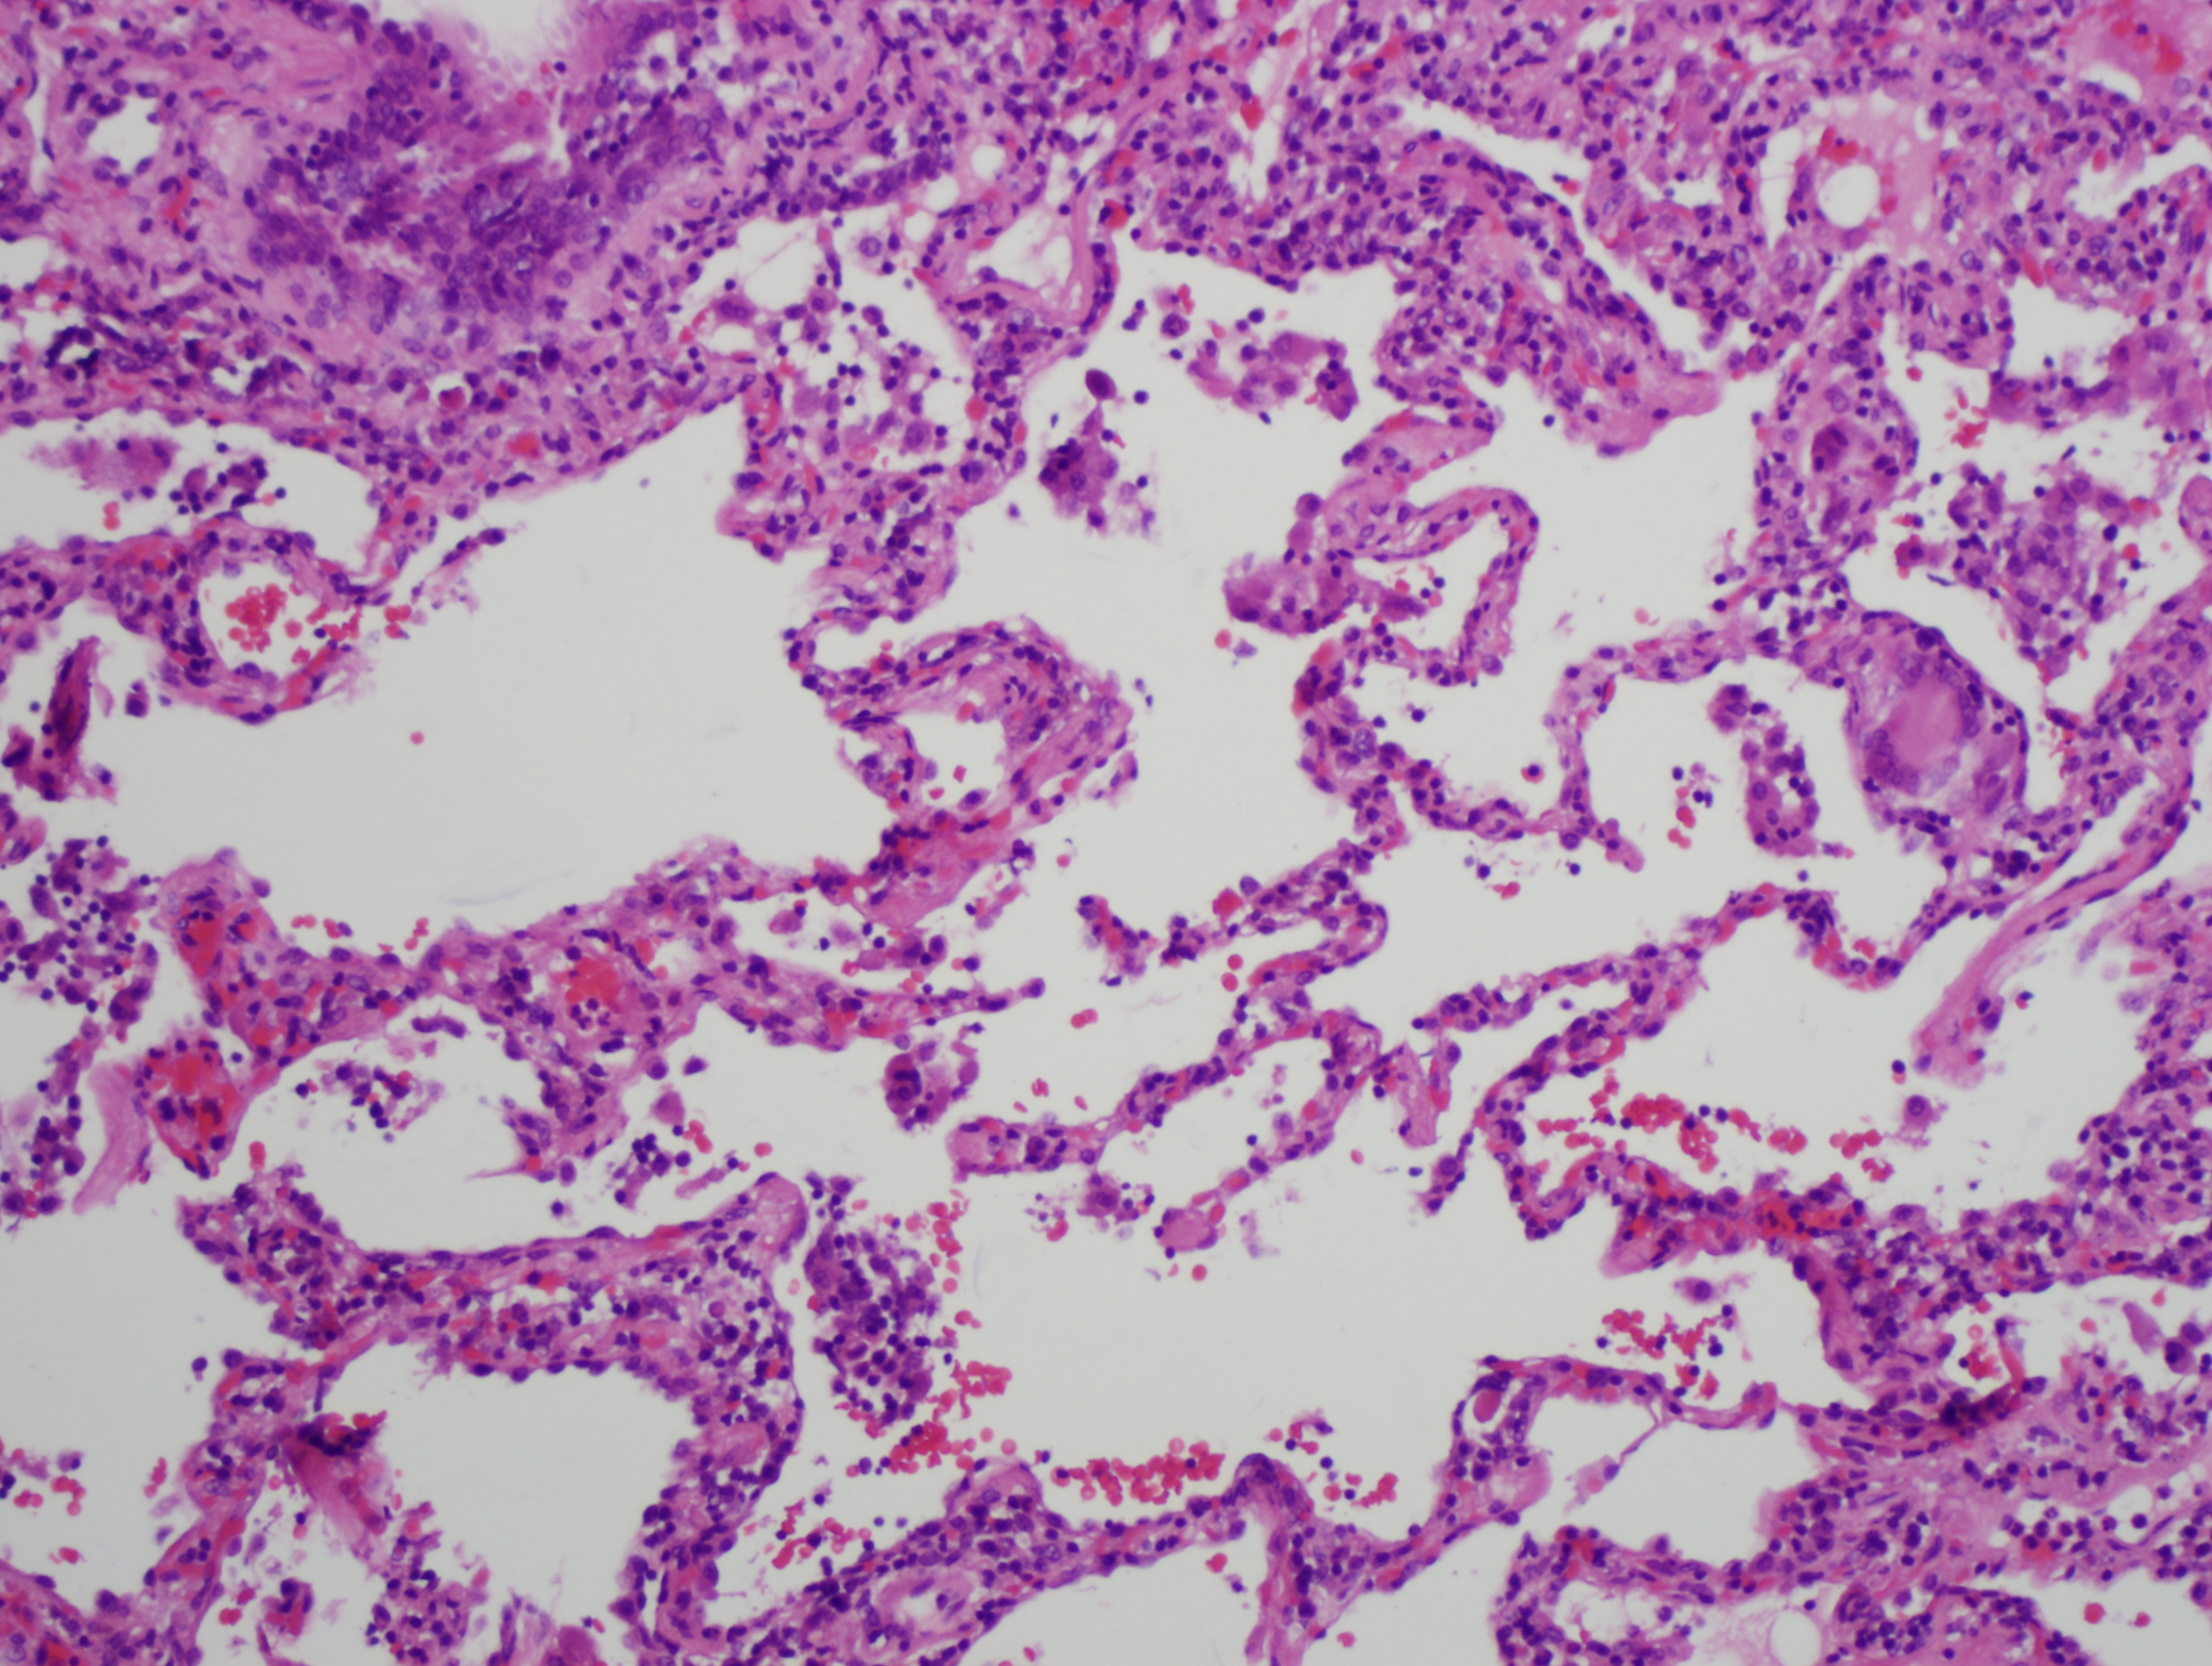

In the acute phase, lymphocytes and macrophages infiltrate the alveolar walls and loose granulomas can form. The presence of multi-nucleated giant cells (figure 8.2), are helpful in diagnosis, but more typical is a dramatic rise in lymphocyte count in BAL fluid, particularly CD8+ cells.

Figure 8.1: Acute phase of hypersensitivity pneumonitis. Note presence of giant cells in the alveolar septum on the center, right-hand side of field of view.